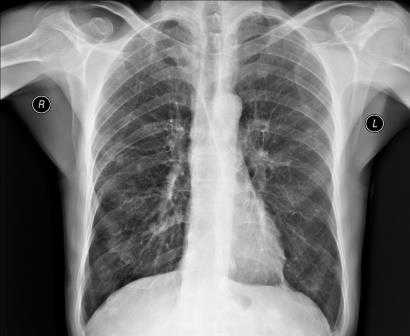

Рентгенография органов грудной клетки в заднепередней (ЗП) проекции: определяется нормальная картина, позволяющая продемонстрировать сложности в интерпретации рентгенограмм грудной клетки. При рентгенографии грудной клетки визуализируется ряд структур и тканей со значительным наложением структур различной рентгенографической плотности. Часть легких может быть перекрыта мягкими тканями средостения и скелетными структурами. Внимание к качеству рентгенограммы играет важнейшую роль в правильной диагностике скрытых аномалий. Рентгенография органов грудной клетки в боковой проекции, ортогональной (под углом 90°) исследованию в ПЗ проекции. Рентгенография в боковой проекции—дополнительная проекция, на которой возможно визуализировать нижнюю долю левого легкого, расположенную позади сердца, и основания легких, расположенные за диафрагмой, она также позволяет оценить грудной отдел позвоночника. Как и при рентгенографии грудной клетки в ПЗ проекции, множество структур с различной плотностью накладываются и должны оцениваться с использованием системного подхода. Анализ рентгенограмм в ПЗ и боковой проекциях позволяет определить анатомическое расположение, оценить патологическое изменения органов грудной клетки и провести полноценную дифференциальную диагностику.

Пневмоторакс обычно четко просматривается на рентгеновских снимках (рис.1). Висцеральная плевральная линия видна без периферического легочного рисунка. Для диагностики сомнительных случаев рекомендуется делать рентгенологическое исследование в боковой проекции или в положении лежа [2]. На стандартном рентгеновском снимке в боковой проекции висцеральная плевральная линия может просматриваться в ретростернальной позиции или лежит на позвонках, параллельно грудной клетке [3]. Рентгенологическое исследование в боковой проекции или в положении лежа можно делать у пациентов, подключенных к аппарату ИВЛ, или у новорожденных. Хотя оценка дыхательной функции довольно противоречива [4], многие врачи считают ее полезной при определении небольших пневмотораксов, когда рентгенологические параметры в норме, но наличие пневмоторакса нельзя исключить. По рекомендациям Британского торакального общества [2] пневмотораксы делят на большие (более 2 см) и маленькие (менее 2 см); расстояние рассчитывается от висцеральной плевры (края легкого) до грудной клетки (стенки). Небольшая воздушная кромка вокруг легкого в действительности преобразуется в достаточно большое снижение легочного обьема, при глубине пневмоторакса в 2 см он занимает почти 50% гемоторакса [2]. Обширный пневмоторакс является объективным показанием для проведения дренирования [2].

Рентгенография грудной клетки должна тщательно изучаться на предмет наличия основного паренхиматозного легочного заболевания (рис. 5). Наиболее распространенными заболеваниями, предрасполагающими к развитию пневмоторакса, являются эмфизема, фиброз легочной ткани любой этиологии, кистозный фиброз, быстро прогрессирующая пневмония или пневмония с распадом легочной ткани, кистозные заболевания легких, такие как клеточный гистиоцитоз Лангерганса и лимфангиомиоматоз. Выявление данных заболеваний очень важно, поскольку: во–первых, паренхиматозное легочное заболевание поддается лечению; во–вторых, в отличие от первичного спонтанного пневмоторакса пациенты с диагнозом вторичного пневмоторакса требуют тщательного стационарного наблюдения [2]. Наконец, все, кроме наимельчайших вторичных пневмотораксов (определенных как верхушечные или менее 1 см в глубину), требуют проведения лечения, даже при минимальных симптомах [2].